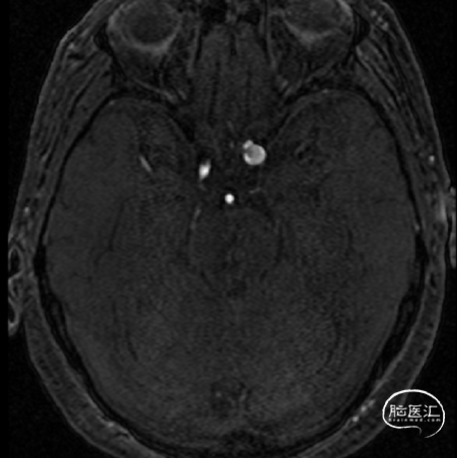

术前影像学检查结果

术前MRI

术前MRA